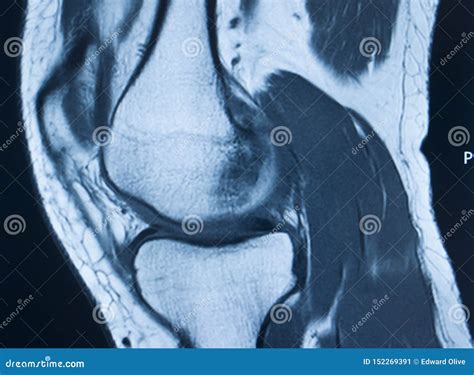

An *Mcl Tear Mri* can help determine the grade of the MCL tear, which is classified as follows:

Grade Description

Grade I Mild tear with minimal damage to the ligament fibers. The knee remains stable.

Grade II Partial tear with more significant damage to the ligament fibers. The knee may feel unstable.

Grade III Complete tear with severe damage to the ligament fibers. The knee is unstable and may require surgical intervention.

An *Mcl Tear Mri* is particularly useful for differentiating between an MCL tear and other knee injuries, such as meniscal tears or anterior cruciate ligament (ACL) injuries. This information is crucial for developing an appropriate treatment plan.